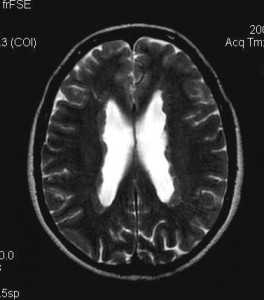

Туберозный склероз. Гамартомы. КТ, Т2-зависимая МРТ и FLAIR

Туберозный склероз (синдром Бурневиля) встречается реже нейрофиброматоза. Его частота по данным литературы составляет около одного на 180 тыс. населения. От 20 до 40% случаев туберозного склероза унаследованы по аутосомно- доминантному типу, остальные возникли вследствии мутаций предположительно 9 и 11 пар хромосом (тип 1), либо 19 пары (тип 2). Поражение может затрагивать практически любые органы. Патогномоничными поражениями ЦНС являются корковые узлы в головном мозге и множественные субэпендимальные глиальные узлы , а также внутрижелудочковая гигантоклеточная астроцитома, встречаются сопутствующие аномалии - агенезия мозолистого тела, пахигирия, аневризмы. Характерны дерматологические проявления в виде множественных ангиофибром лица в форме «бабочки», бледные пятна на лице и груди, фибромы кожи, под ногтями и сетчатке глаза. Из других проявлений встречаются множественные ангиолипомы почек и печени, рабдомиомы сердца, лимфангиоматоз лёгких, костные склеротические и кистозные изменения. Диагноз туберозного склероза ставится при наличии у пациента 2 из перечисленных характерных признаков.

Корковые узлы - самое частое проявление туберозного склероза. Они расположены в коре головного мозга, деформируют её, захватывают прилегающее белое вещество и подвергаются кальцификации . При МРТ узлы изоинтенсивны серому веществу на Т1-взвешенных МРТ и чуть гиперинтенсивнее его на Т2-взвешенных. Контрастирование наблюдается в 5% случаев. В белом веществе обнаруживаются тяжи , отходящие радиально от желудочков. Корковые узлы и тяжи нередко называют «гамартомами», хотя они представляют собой скорее демиелинизацию и кальцификацию, чем истинную гетеротопию.

Субэпендимальные, то есть проецирующиеся в желудочек, но растущие со стороны паренхимы мозга, узлы чаще расположены рядом с хвостатым ядром или гипоталамической бороздой сразу за отверстием Монро, реже в области III, IV желудочков и Сильвиева водопровода. На Т2-взвешенных томограммах субэпендимальные узлы умеренно гиперинтенсивны и часто содержат кальцинаты . От астроцитом их отличает не столь яркий сигнал и меньшие размеры. Контрастирование при введении препаратов гадолиния иногда наблюдается и в субэпендимальных узлах , и всегда в астроцитомах.